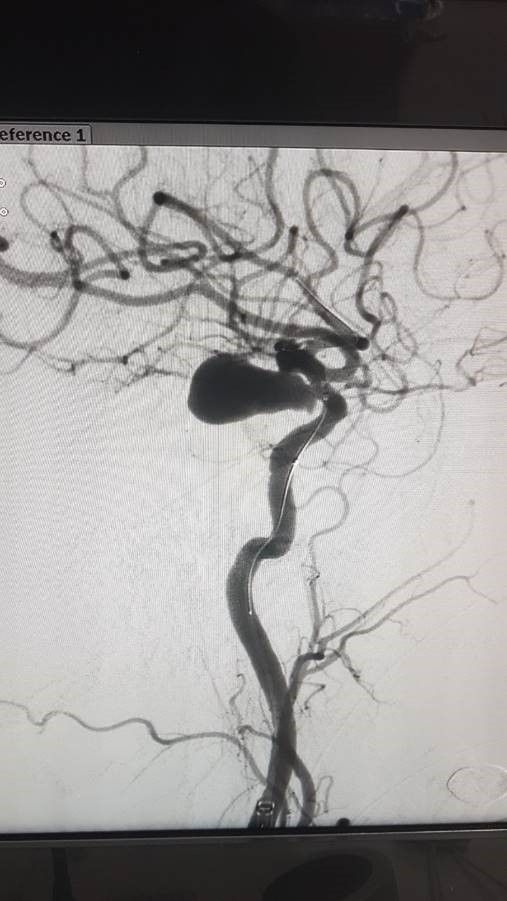

- metode de clipare la nivelul coletului anevrismului (după craniotomie) – tipuri de clipuri (similare unor clame, agrafe): McFadden Vari-Angle, Yașargil, Hernesniemi, Sugita etc. (fig. 1);

Fig. 1: Anevrism clipat de arteră comunicantă anterioară (din arhiva personală a prof. dr. A.V. Ciurea).